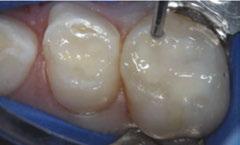

The 5-year-old patient featured in this case study did not benefit from early oral care and had multiple carious lesions. Considering the young age, high caries risk, and the uncertainty of compliance with follow-up appointments, I wanted to restore and seal all teeth in one visit. One quadrant is shown in this case study. The carious lesion on tooth J (65) was cavitated and prepared, restored, and sealed. Tooth I (64) was non-carious and would only be sealed (Figure 1).

surface of tooth I (64) was also lightly abraded with a diamond bur (Figure 2). The preparations were selectively etched with phosphoric acid, rinsed, and lightly dried (Figure 3). Bonding agent was applied to the entire occlusal surfaces of both teeth, air thinned, and light-cured (Figure 4).

Tooth J (65) was bulk-filled with Activa Kids. For this fast injection technique, I place the dispensing tip at the floor of the preparation and extrude the material without removing the tip until the preparation is completely filled (Figure 5). I like to do some minor manipulation of the filling material with hand instruments to create anatomy, as well as to ensure the material is flush with the surface of the preparation, and no air is trapped inside. Activa Kids is dual-cure, ideal for bulk filling, and can be cured with all lights. A thin topcoat of Activa Presto was placed as a sealant on the entire occlusal surface of teeth I and J (64 and 65) (Figure 6). Figure 7 shows the final clinical situation.

Figure 1 (left): Caries lesion on tooth J (65). Figure 2 (center): Preparation of tooth J (65) and abraded occlusal surface of tooth I (64). Figure 3 (right): Selective etch of enamel Figure 4 (left): Bonding agent is applied to both teeth I and J (64 and 65). Figure 5 (right): The preparation is filled with ACTIVA Kids Figure 6 (left): A thin topcoat of ACTIVA Presto is applied to the occlusal surfaces of teeth I and J (64, 65). Figure 7 (right): Final result